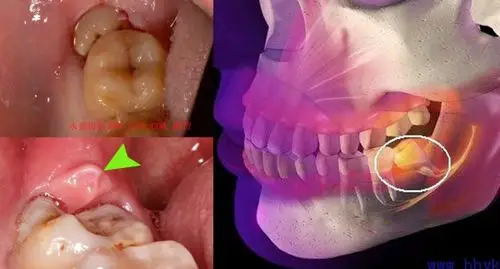

智齿可能导致的危害

智齿不拔究竟会有什么后果?

不拔智齿的人你们会后悔的

对于长智齿,看是否长歪或者经常发炎,如果影响口腔的健康建议拔掉

顽固的智齿到底该不该拔呢?多年来疑惑终於有解了!通常你不正视.